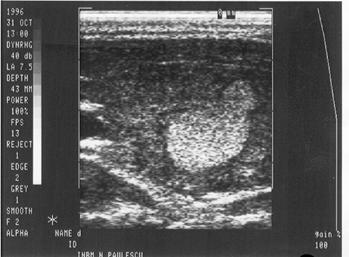

Figura 5. Hemangiom hepatic lobul stang

Figura 6. Hemangiom renal - la nivelul treimii medii a

rinichiului drept, mica zona hiperecogena, rotunda, care deformeaza conturul

renal.

Figura 7. Litiaza biliara

Figura 8. Litiaza coledociana